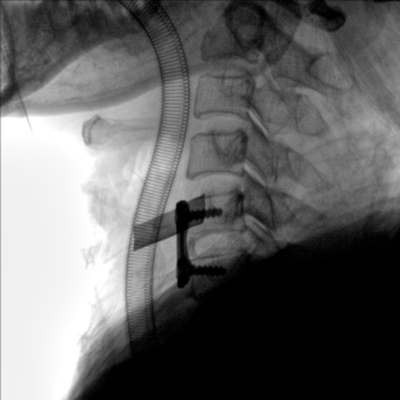

大尺寸動態(tài)平板探測器,高DQE、低噪聲、圖像清晰。采用多分辨率圖像增強(qiáng)處理技術(shù),不同部位不同圖像處理算法,滿足客戶多樣化的需求。

采用智能變頻脈沖透視技術(shù),優(yōu)化圖像質(zhì)量的同時降低輻射劑量,呵護(hù)醫(yī)患健康